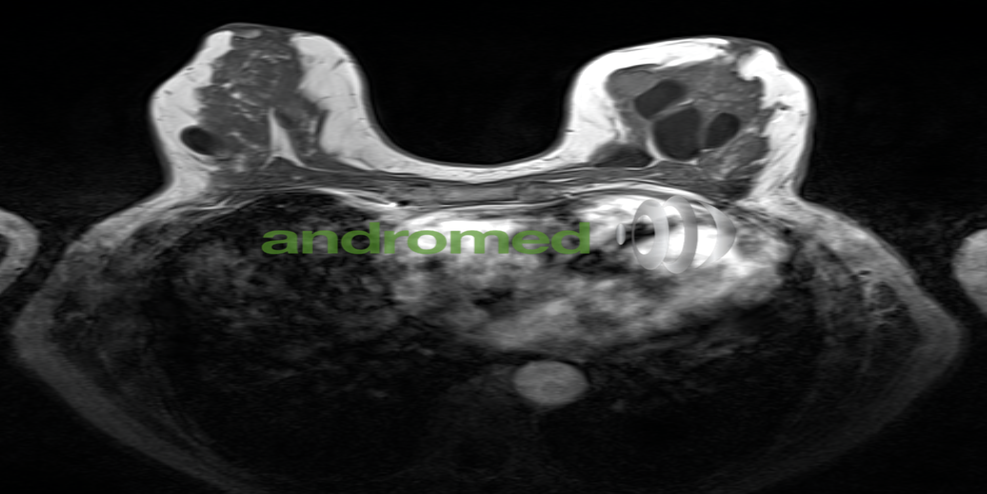

Diagnose im Bild: MRT-Diashow

4. Urologie: Die MRT ist in der Urologie von zentraler Bedeutung. Sie liefert detailreiche und strahlungsfreie Bilder der Prostata, Nieren, Blase, Hoden und anderer relevanter Strukturen. Die präzisen Ergebnisse der MRT sind unverzichtbar bei der Früherkennung von Prostatakrebs sowie der Beurteilung von Nierenerkrankungen. Dank ihrer Genauigkeit und Strahlungsfreiheit gilt die Magnetresonanztomographie als unverzichtbares Instrument für die präzise Diagnostik und Planung in der Urologie.

5. Abdominal- und Beckenuntersuchungen: In der Abdominaldiagnostik liefert die MRT detailreiche Bilder der Bauchorgane, einschließlich Leber, Bauchspeicheldrüse, Nieren, Gallenblase und Darm. Die MRT wird zur Erkennung von Lebertumoren, Nierensteinen, entzündlichen Darmerkrankungen und zur Stadieneinteilung von Tumoren im Magen-Darm-Trakt eingesetzt.